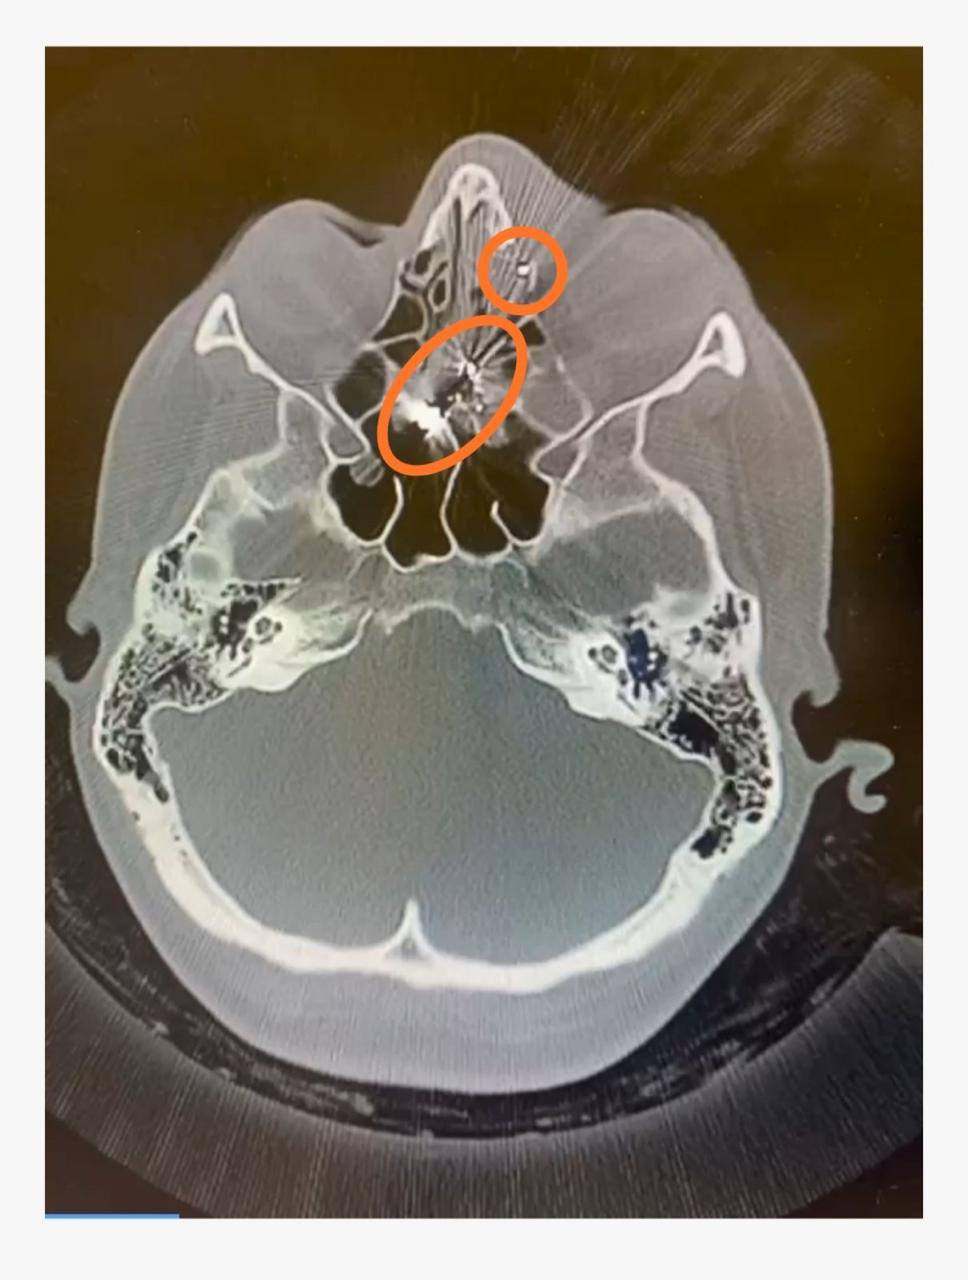

Лікарі швидкої надали екстрену медичну допомогу, а потім доправили поранену до Кам’янської лікарні швидкої медичної допомоги. Під час комп’ютерного обстеження було виявлено проникаюче кульове пневматичне поранення лівої очниці.